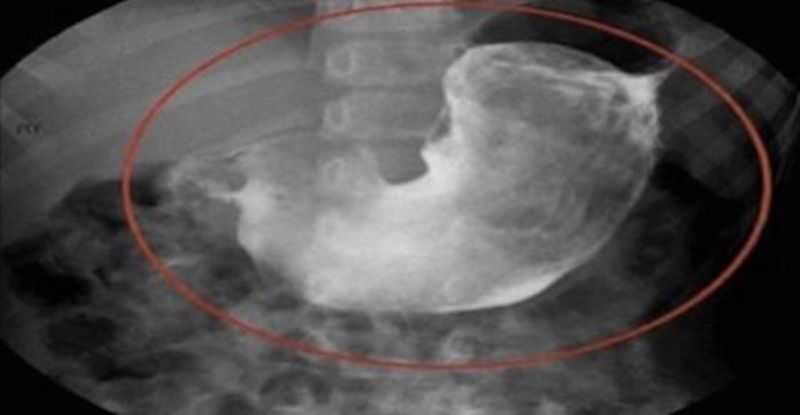

O femeie a ajuns la ginecolog cu dureri mari de burta. Michelle Barrow nu mai suporta durerile din zona abdomenului si si-a facut o programare la medicul ginecolog. Specialistul a crezut ca ar putea fi vorba de chisturi ovariene, dar in urma consultului a facut o descoperire care l-a socat: a gasit un ghemotoc de par!

Pacienta a inteles imediat ce se intamplase. A recuscut fire din parul uneia dintre cele doua pisici ale familiei. Michelle Barrow a aflat cum a ajuns ghemotocul de blana in abdomenul ei. Dupa o discutie cu ginecologul, a inteles ca parul pisicii care obisnuia sa doarma in acelasi pat cu ea si partenerul ei a ajuns pe organul sexual al iubitului, apoi in vaginul ei, dupa care a migrat in interiorul abdomenului.

Medicul a sfatuit-o sa fie mai atenta cu igiena intima. Specialistul i-a recomandat sa nu mai lase pisicile sa doarma pe asternuturi, sa schimbe cearsafurile mai des si sa faca dus inainte de momentele intime, atat ea, cat si partenerul de viata.